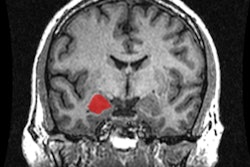

The left ventricle is the main pumping chamber of the heart and has been known to be a predictor of cardiovascular health. Previous research has shown that left ventricular mass can increase or decrease with age, but many of these studies focused on one point in time and young versus older patients, without accounting for lifestyle or other factors.

From an imaging standpoint, echocardiography has been the modality of choice to visualize the heart, but it's difficult to delineate the boundary of the wall and the blood inside the heart with this modality.

Dr. John Eng from Johns Hopkins University."Cardiac MRI is a 3D imaging technique that can detail where that boundary is," Eng explained to AuntMinnie.com. "It is a more precise way to measure the mass of the heart and the chamber volumes."

Thus, the purpose of the current study was to use cardiac MRI to evaluate age-related left ventricular changes over time in a large cohort of asymptomatic people with no evidence of cardiovascular disease.